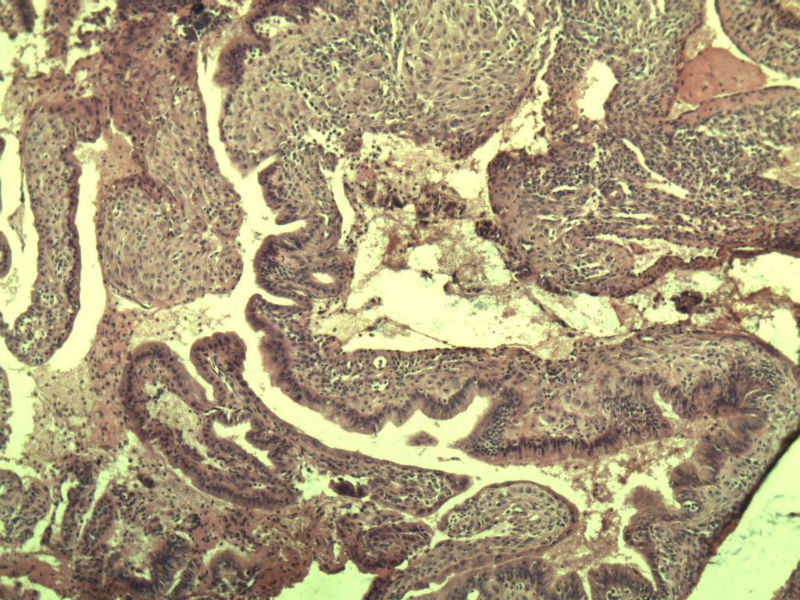

女 32岁 不规则阴道流血 一年  请各位老师看看 谢谢了

遵义医学院附属医院会诊结果    "复杂性增生伴非典型性 "

补充一下病史 病人10个月前因月经不规则行诊刮 诊断非典型性增生  上了曼月乐避孕环(好像是缓慢释放孕激素的那种),         都用激素治疗大半年了 还是这个样子 我还是觉得是癌  只有追踪一下以后病人的情况吧

高分化子宫内膜样癌

非典型复杂性子宫内膜增生,应了解雌孕激素情况。

子宫内膜复杂性非典型性增生,局灶区间质肉芽样(图5)及蜕膜样变,不够癌,建议临床查激素水平并追踪。

从照片看,没看到浸润的地方,我考虑是子宫内膜重度不典型增生。